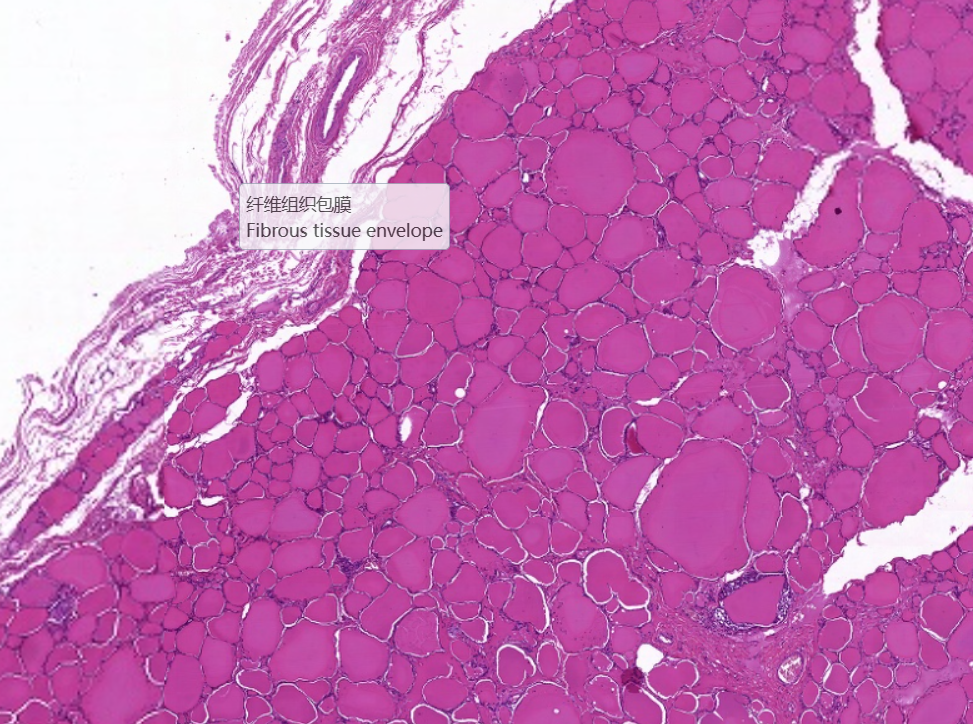

弥漫性非毒性甲状腺肿:甲状腺滤泡明显扩张,内含大量胶质,滤泡上皮细胞受压呈扁平状。部分上皮增生,可见小滤泡和小假乳头形成。

1.全景图

![]()

2.纤维组织包膜

3.滤泡上皮增生

4.滤泡扩张